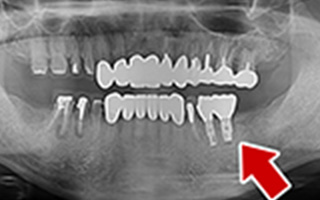

Before

After

| 68歳 男性 | 紹介 |

|---|---|

| 主訴 | れ歯が合わない 食べにくい 人生を豊かにしたい |

| 処置内容 |

上顎4本で12歯(オールオン4)、下顎4本5歯 上下抜歯即時埋入、即時荷重(手術当日にインプラントの上に仮歯装着) |

| 治療費用 | 上顎: 約220万(税込) 下顎: 約180万円(税込) |

| 治療期間 | 上顎: 9ヶ月 下顎: 6ヶ月 |

| リスク |

術後の腫れ、痛み(ピークは3日後、1週間で軽減) 上部構造物、仮歯の破折、人工歯根脱落リスクがあります |